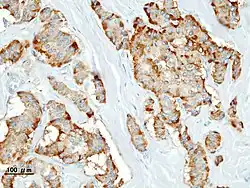

Гистологическая картина

- Патогистология

Панкреатическая инсулинома Окраска инсулиномы Chromogranin A - Histopathology of pancreatic endocrine tumor (insulinoma). Insulin immunostain.